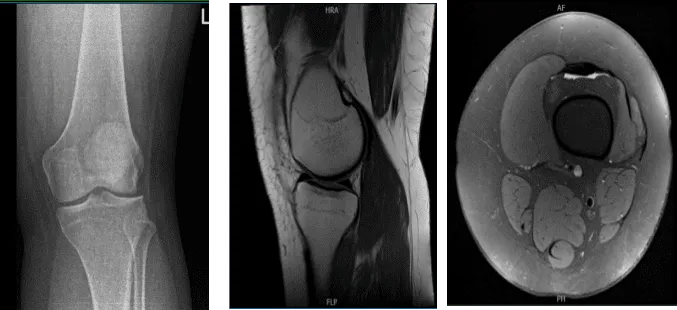

Su radiografía no mostró cambios degenerativos significativos ni fracturas agudas. Acordamos hacernos una resonancia magnética que mostró un desgarro en el menisco lateral con el mango del cubo.

Resonancia magnética de la rodilla izquierda